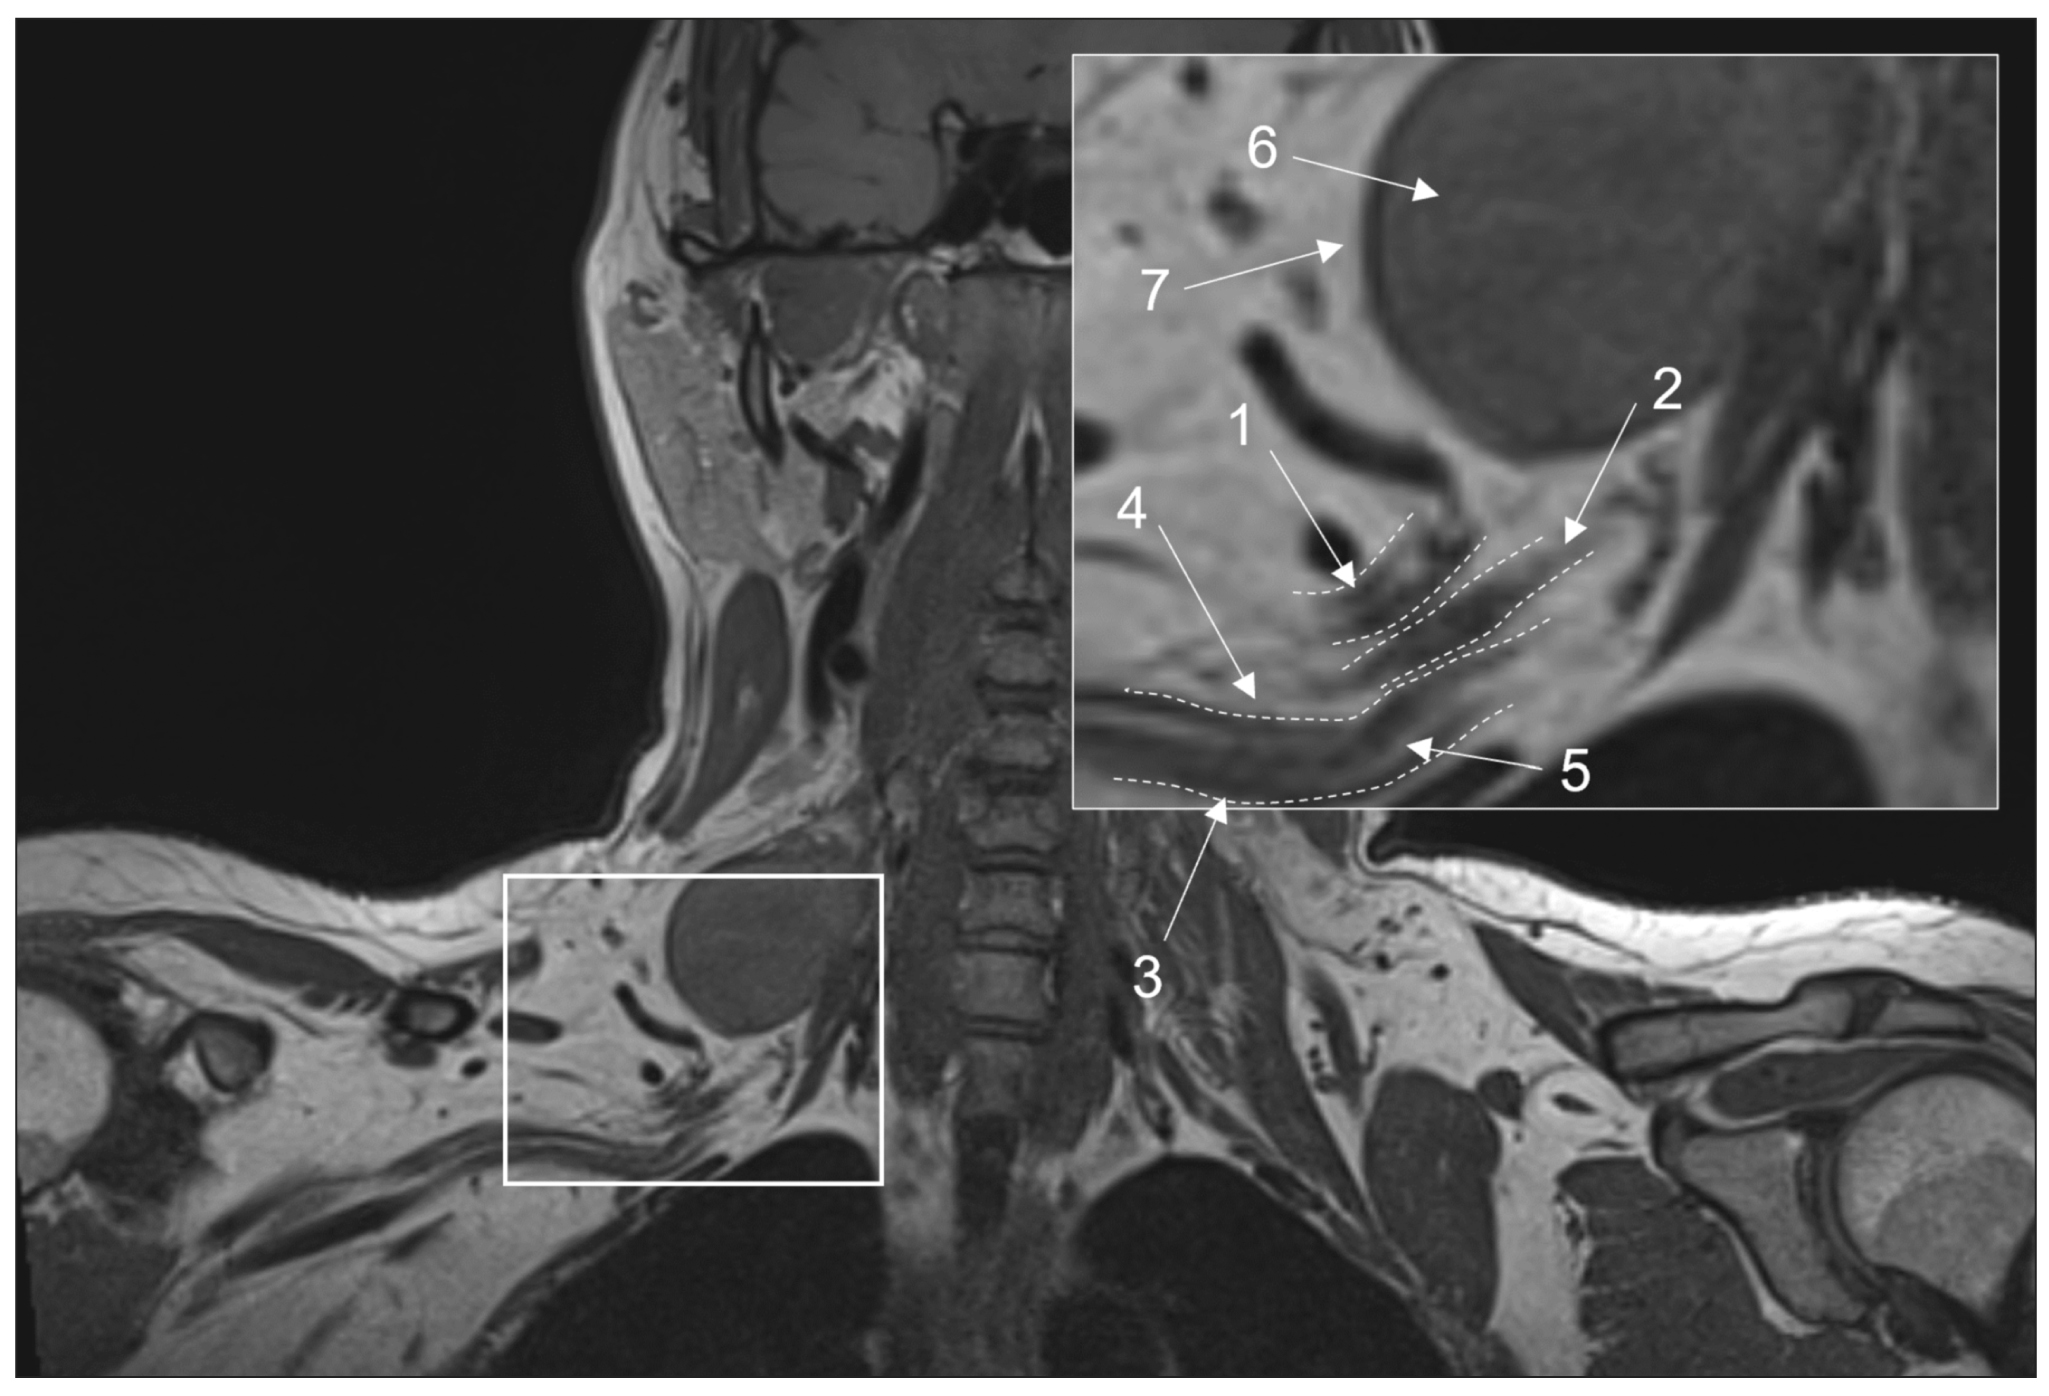

Conventional magnetic resonance imaging of peripheral nerves: MR-neurography

Peripheral neuropathy is known to be one of the most common neurological disorders. Despite the great diagnostic value of electroneuromyography and ultrasound, addressing the diagnostics and differential diagnostics of peripheral nerve diseases of different origin could be challenging. In recent years, magnetic resonance tomography has been increasingly used for evaluating cases of suspected or established peripheral neuropathy with excellent results.

This manuscript mainly deals with the advantages and limitations of the aforementioned diagnostic instruments, technical considerations according to different anatomy of peripheral nerves, along with state-of-the-art technical decisions, frequently used magnetic resonance imaging sequences and their diagnostic value based on own observation, and recommendations for contrast enhancement use and different methods of fat suppression.

Currently, there is practically no standardized description of normal magnetic resonance imaging features of peripheral nerves, as well as their changes in different diseases. The evaluation of images is mainly based on the radiologist experience, which obviously decreases method’s diagnostic value. Studies of large numbers involving healthy volunteers and patients with peripheral neuropathies of different origin are required to address this issue.